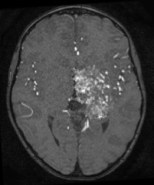

la décision de traitement semble donc une option raisonnable, surtout pour des lésions particulièrement dangereuses comme les MAV du cervelet.